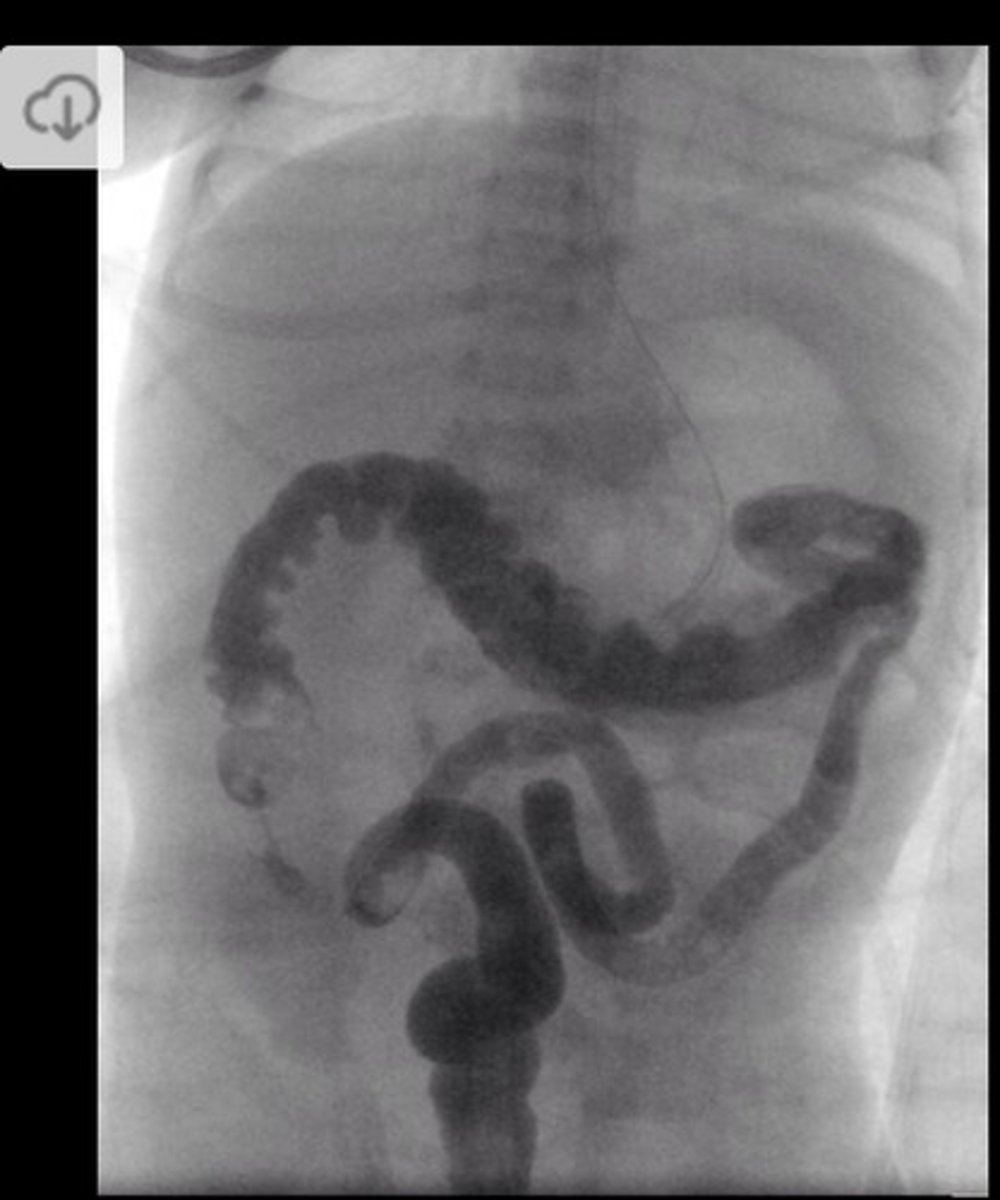

What is the best initial diagnostic test for suspected malrotation/midgut volvulus, & what must this be followed up by? What will be seen?

Initial: abdominal x-ray - double bubble sign and/or air-fluid levels (remember need to d/dx duodenal atresia from this)

Best: upper GI contrast series/contrast enema - twists of barium w/ bowel pushed over to the right